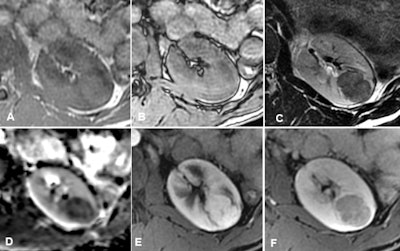

The new mpMRI protocol in play at Bordeaux for differentiation is now being validated for diagnostic accuracy. In the protocol, the most useful sequences for characterization are as follows:

- T2-weighted sequences: These must be performed strictly with turbo or fast spin echo and never in T2-weighted fast gradient echo. This allows the evaluation of the tumor's signal strength compared with the kidney. Only fat-poor angiomyolipoma (fpAML) and type 1 papillary carcinoma have a much lower signal than the kidney.

- T1-weighted gradient-echo sequences with chemical shift (Dixon) imaging: A drop in signal can be seen in opposed-phase in cases of fpAML, clear cell carcinoma, or papillary carcinoma and in in-phase images in cases of papillary carcinoma.

- Diffusion sequences: With these also, only cases of fpAML and papillary carcinoma have a much lower signal than the kidney.

- Dynamic sequences after injection of contrast media allow the "plotting" of enhancement: Only cases of papillary carcinoma show very poor and very progressive enhancement.

Through comparing and combining these different criteria, radiologists can arrive at different, more specific diagnoses, Grenier noted.